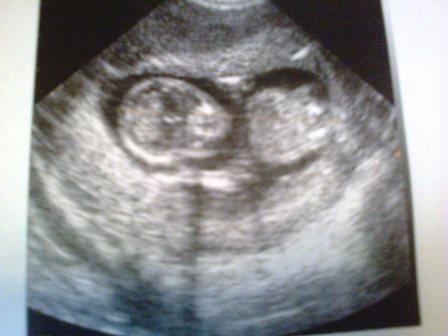

Нам уже 13 неделек))

УЗИ, КТГ, доплерну вот нам уже 13 неделек видела нашу лялячку пока кто не ясно но у нас все замечательно,единственное токсикоз меня не отпускает,ну и фото))